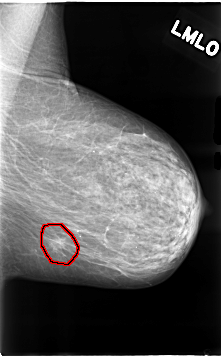

C_0049_1.LEFT_MLO

LEFT_MLO LINES 4640 PIXELS_PER_LINE 2872 BITS_PER_PIXEL 12 RESOLUTION 50 OVERLAY

FILE: C_0049_1.LEFT_MLO.OVERLAY

TOTAL_ABNORMALITIES 1

ABNORMALITY 1

LESION_TYPE MASS SHAPE IRREGULAR MARGINS SPICULATED

ASSESSMENT 5

SUBTLETY 5

PATHOLOGY MALIGNANT

TOTAL_OUTLINES 1

BOUNDARY